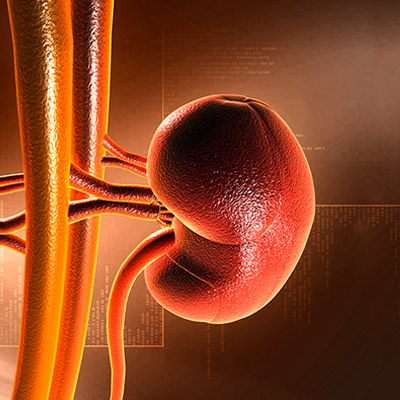

SOINS CLINIQUES DE POINTE

L’activité clinique est exercée de manière exhaustive au sein d’unités et d’équipes interdisciplinaires appliquant des protocoles et processus de qualité s’appuyant sur les meilleurs éléments scientifiques disponibles.

PROFESSIONNELS

Le savoir et l’expérience acquis durant plus de 100 ans et s’accompagnant d’une vision exhaustive ont permis à nos professionnels de se placer dans une position de leadership et de référence en ce qui concerne les pathologies les plus complexes.